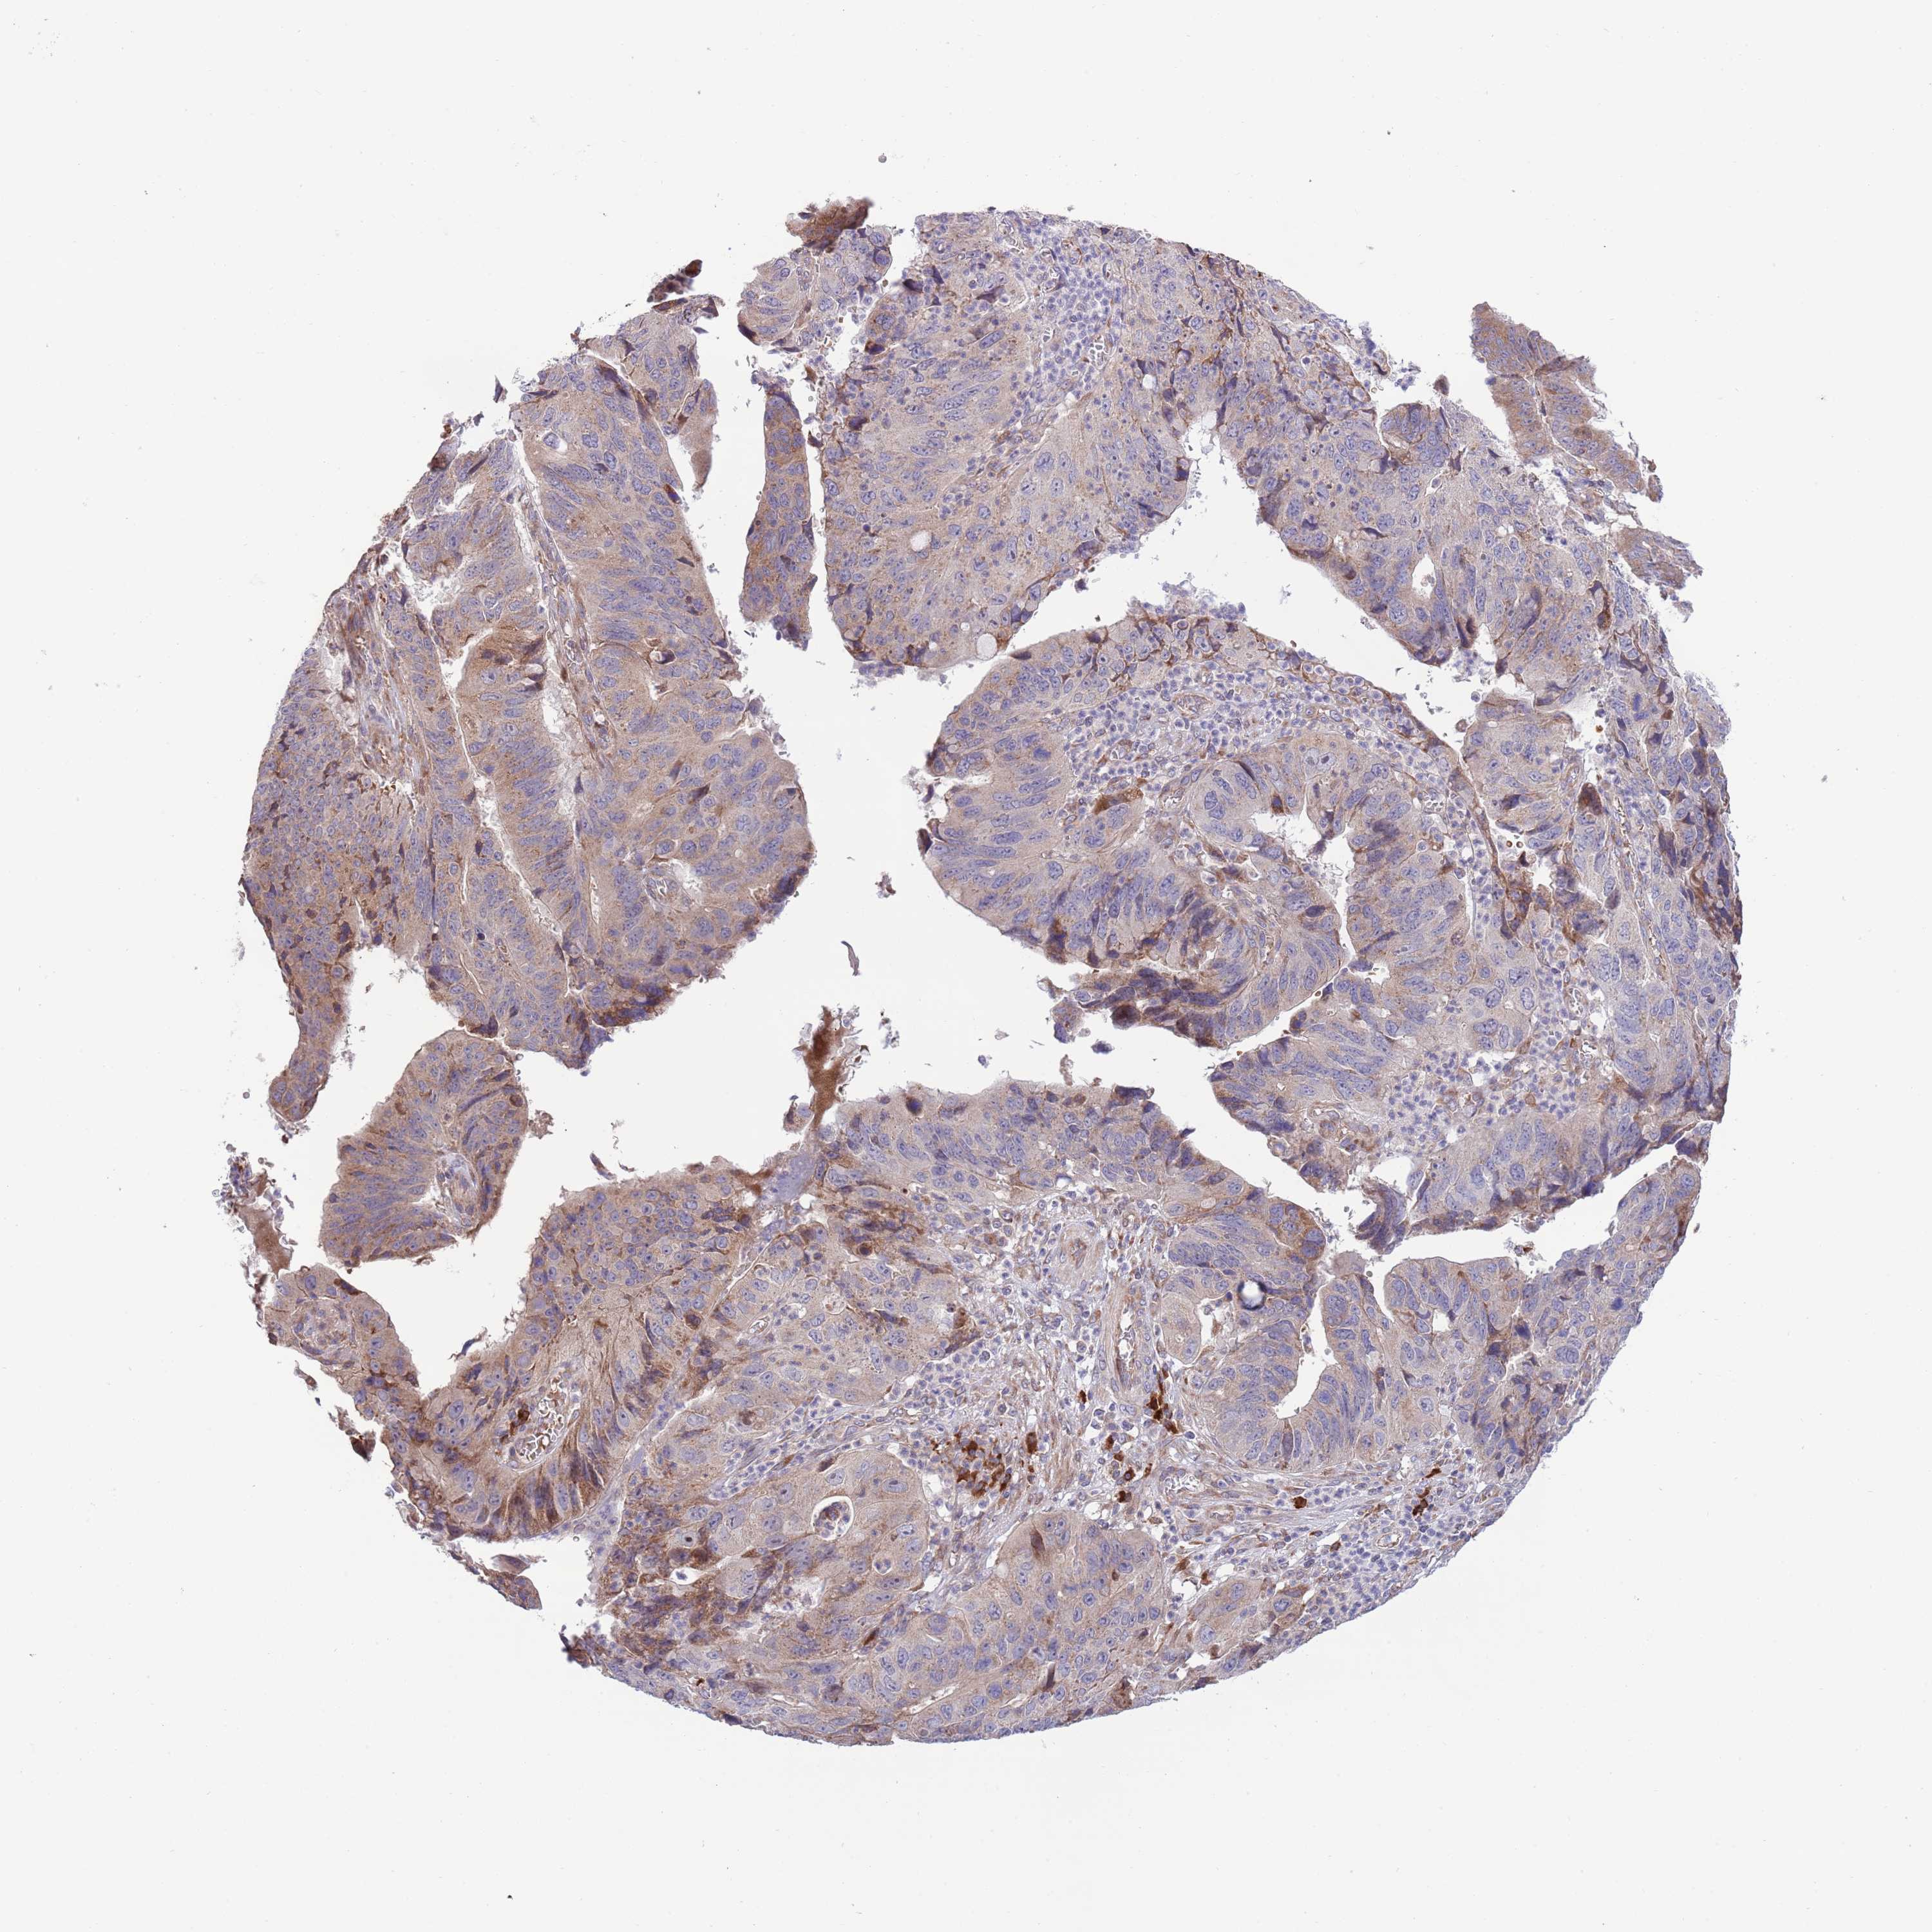

STOMACH CANCER - Protein expressioni

A mouse-over function shows sample information and annotation data. Click on an image to view it in a full screen mode. Samples can be filtered based on level of antibody staining by selecting one or several of the following categories: high, medium, low and not detected. The assay and annotation is described here.

Note that samples used for immunohistochemistry by the Human Protein Atlas do not correspond to samples in the TCGA dataset.

Antibody stainingi

Antibody staining in the annotated cell types in the current human tissue is reported as not detected, low, medium, or high, based on conventional immunohistochemistry profiling in selected tissues. This score is based on the combination of the staining intensity and fraction of stained cells.

Each image is clickable and will lead to virtual microscopy that enables deeper exploration of all samples and also displays staining intensity scores, fraction scores and subcellular localization as well as patient and tissue information for each sample.

Antibody HPA049472

Staining

High

Medium

Low

Not detected

Intensity

Strong

Moderate

Weak

Negative

Quantity

>75%

75%-25%

<25%

None

Location

Nuclear

Cytoplasmic/membranous

Cytoplasmic/membranous,nuclear

Adenocarcinoma, NOS